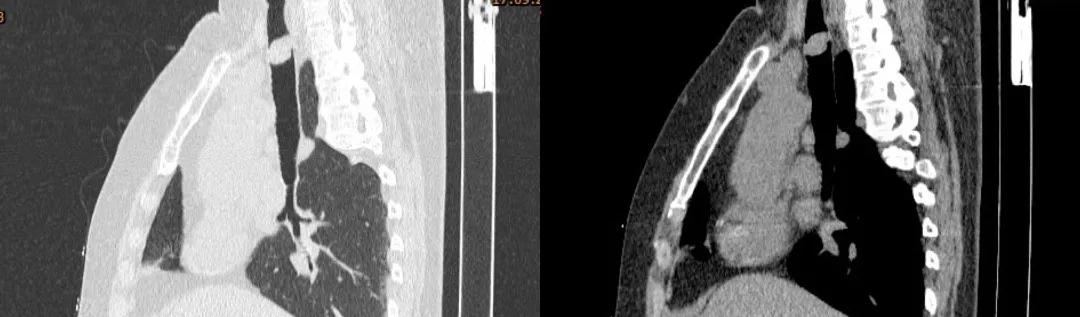

胸部CT:

胸部CT(矢状位)

四、影像学检查:表现为气管腔内的软组织密度肿块

表现为气管腔内的软组织密度肿块,多为偏心性,好发于气管后壁、气管软骨,低中度均匀强化,伴气管壁增厚,管腔不规则狭窄。有时可见气管旁淋巴结肿大,提示肿瘤转移可能。晚期可血行转移至肺、骨、脑、肝脏。